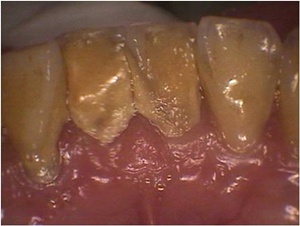

이러한 의료 및 경제적 문제에서 구강건강이 차지하는 부분은 적지 않다. 실제 의료보험공단에서 지출되는 비용 중 잇몸질환과 관련된 비용은 항상 상위권을 차지하고 있다. 이러한 잇몸질환의 경우 나이가 들수록 증가하는 추세를 보이며 잇몸질환으로 인해 치아를 발치해야하는 경우도 증가하고 있다. 즉 잇몸질환으로 인한 치아의 발치와 이로 인한 임플란트나 틀니등의 치료비용은 증가할 수밖에 없는 실정이다. 그리고 이러한 치료는 고가의 치료비로 인해 많은 노인분들에게 큰 어려움을 주고 있는 것이 현실이다.

그럼에도 불구하고 많은 사람들이 여러 가지 이유로 스케일링 받기를 꺼려하는 것이 사실이다. 그중에는 치료 후 불편감이나 오해등에 기인하는 경우가 많다. 스케일링 후에 일시적으로 이가 시린 경우도 있고 이가 흔들리는 경우도 있으나 이것은 건강한 상태로 진행되는 일시적 과정이다. 또는 스케일링은 한번 받으면 계속 받아야 한다거나 치아가 파인다거나 하는 등등의 잘못된 이유들로 꺼리는 경우도 있다.

치석이라는 것이 아무리 잇솔질을 잘해도 일정부분 치아에 생기기 때문에 스케일링을 통해 정기적으로 제거해 주는 것은 중요하다. 그리고 이러한 스케일링 치료만 잘해주어도 발치까지 가는 중증의 잇몸질환을 상당부분 예방할 수 있다. 많은 이들이 노후를 위해서 연금보험등 경제적 문제에만 관심을 갖고 있지만 행복하고 건강한 삶을 위해 구강건강유지 또한 간과할 수 없는 요소다. /생활경제팀 osenlife@osen.co.kr